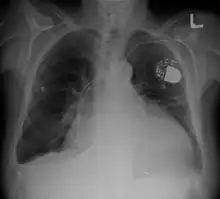

Cardiomegaly on chest X-ray with a pacemaker

• Pacemaker: Coordinates contractions between ventricles. In people at risk of arrhythmias, drug therapy or an implantable cardioverter-defibrillator (ICD).

• ICDs: Small devices implanted in the chest to monitor heart rhythm and deliver electrical shocks to control abnormal heartbeats. The devices can also work as pacemakers.